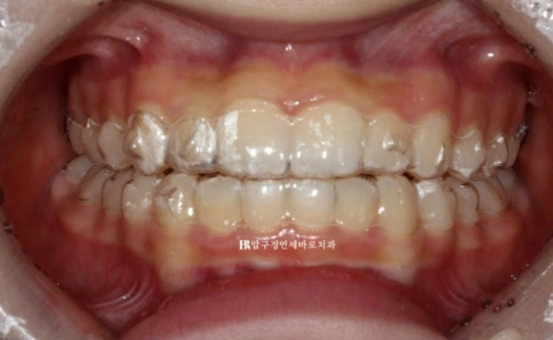

24.02

그리고 지난 달 치료가 마무리 되었습니다.

깊게 물리던 과개교합과 덧니가 깔끔하게 치료가 되었습니다.

덧니가 다시 재발이 되지 않도록 고정식 철사 유지장치도 붙이고 정기검진을 합니다.